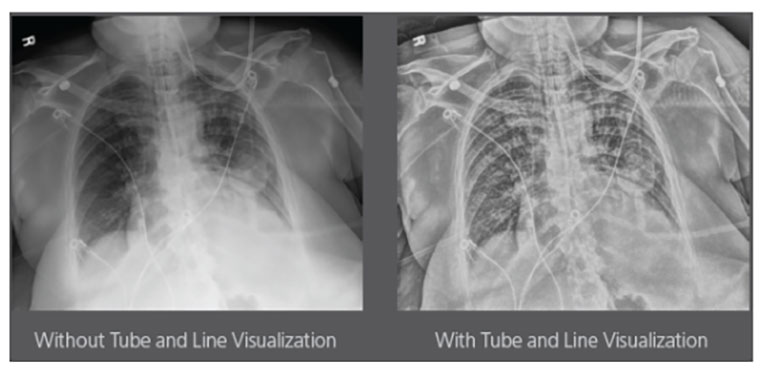

Carestream Introduces New Software Update to Boost Diagnostic Accuracy

Carestream today announced the latest update to its Image Suite V4 Software, MR 11: a series of enhancements to help improve customer confidence and increase diagnostic accuracy [...]

CARESTREAM Image Suite V4 MR11 has set a new standard for workflow efficiency, offering a robust set of features and functionalities to enhance clinical confidence in healthcare professionals. Using an auto-generated companion image from a single exposure, leverage a range of image processing options to increase diagnostic accuracy and enhance patient care.